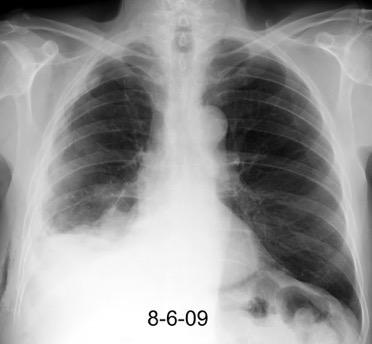

Marzo 2014: Perforación longitudinal distal secundaria a episodio de vómito (síndrome de Boerhaave). Derrame pleural izdo. que evoluciona a empiema.

Wang C-T et al. Tension hydropneumothorax in a Boerhaave syndrome patient: A case report . World J Emerg Med, 2021. Katabathina V et al. Nonvascular, nontraumatic mediastinal emergencies in adults:a comprehensive review of imaging findings. Radiographics. 2011.